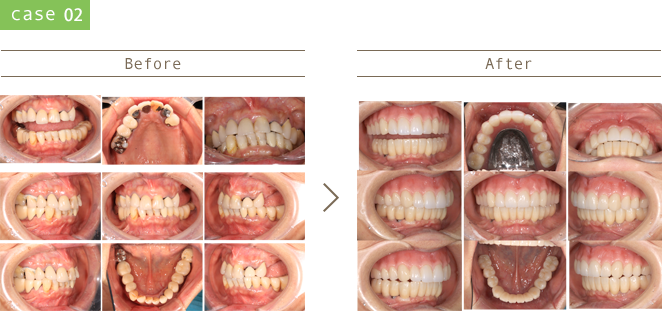

治療後20年・30年後を考え、患者さんが一生噛めることを目指した治療計画を心がけています。

審美的、骨格的、機能的、生態的な観点を包括的に鑑みて治療を行っています。

虫歯の再発リスクの少ない治療、歯周病の発症・進行を防ぐためのメンテナンスに注力しています。